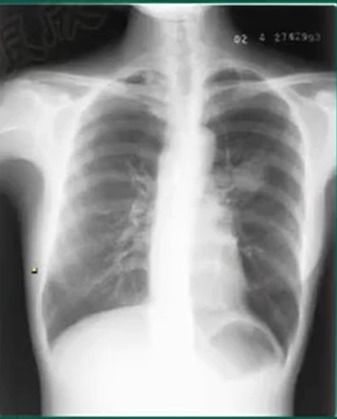

在日新月异的医疗科技浪潮中,医学影像扮演着越来越重要的角色,尤其是在胸部疾病的诊断领域。胸片,作为最常用、最基础的影像学检查手段之一,其质量的好坏直接关系到诊断的准确性。传统的胸片成像过程中,由于患者体位、呼吸配合程度、设备参数设置等多种因素的影响,常常会出现曝光不足或过度曝光的情况,这无疑给医生的阅片带来了巨大的挑战,甚至可能导致漏诊或误诊。

正是在这样的背景下,“100%胸片曝光软件官方版🔥”应运而生,它不仅仅是一款软件,更是医学影像领域的一次重大革新。这款官方发布的软件,凝聚了前沿的图像处理技术与人工智能算法,旨在彻底解决传统胸片成像中的痛点,让每一张胸片都能够以最清晰、最完整、信息量最大的状态呈现在医生眼前。

“100%胸片曝光软件官方版”最令人瞩目的核心功能之一,便是其强大的智能曝光优化能力。通过先进的图像识别算法,软件能够自动分析输入胸片的曝光情况,并进行精准的调整。

智能识别曝光异常:软件能够区分并识别出曝光不足(图像过暗,细节丢失)和曝光过度(图像过亮,细节模糊)的区域。这不仅仅是简单的亮度对比度调整,而是基于对X射线衰减特性的深度理解,能够准确判断图像信息是否因曝光问题而受损。自适应图像增强:针对不同程度的曝光问题,软件会采🔥用不同的增强算法。

对于曝光不🎯足的图像,它能有效提升暗部细节,让隐藏在阴影中的病🤔灶无处遁形;对于曝光过度的🔥图像,则能削减高光区域的噪点,恢复高密度组织的纹理。保留真实信息,避免过度处理:与一些简单的滤镜不同,“100%胸片曝光软件官方版”在进行图像增强时,始终以保留原始医学信息为首要原则。

它旨在“修复”因曝光不足或过度而丢失的信息,而非“创造”不存在的信息。这意味着,软件的优化是基于科学的图像重建原理,而非主观的艺术加工,确保了诊断的客观性。标准化输出💡,提升阅片效率:经过软件优化处理的胸片,曝光情况更加均匀、清晰,这大大降低了医生在阅片时的视觉疲劳,也缩短了诊断时间。